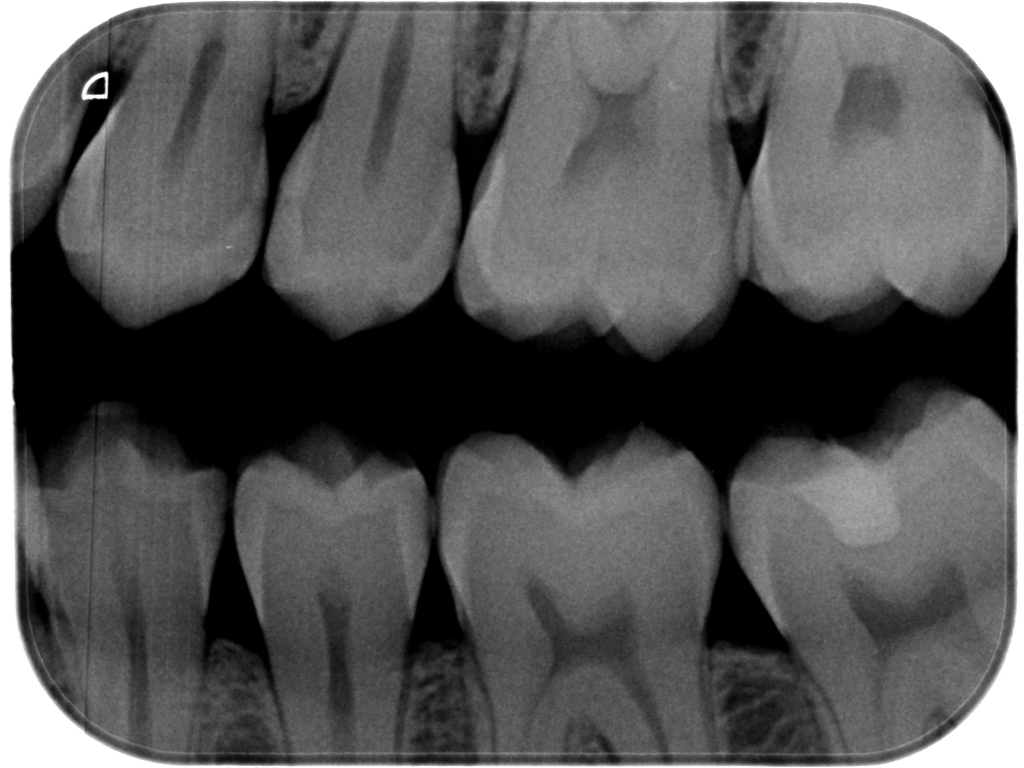

Dental X-ray showing multiple upper and lower teeth with visible roots and crowns

Pre-op bitewing radiograph: it’s possible to appreciate the D1 lesions on the premolars.